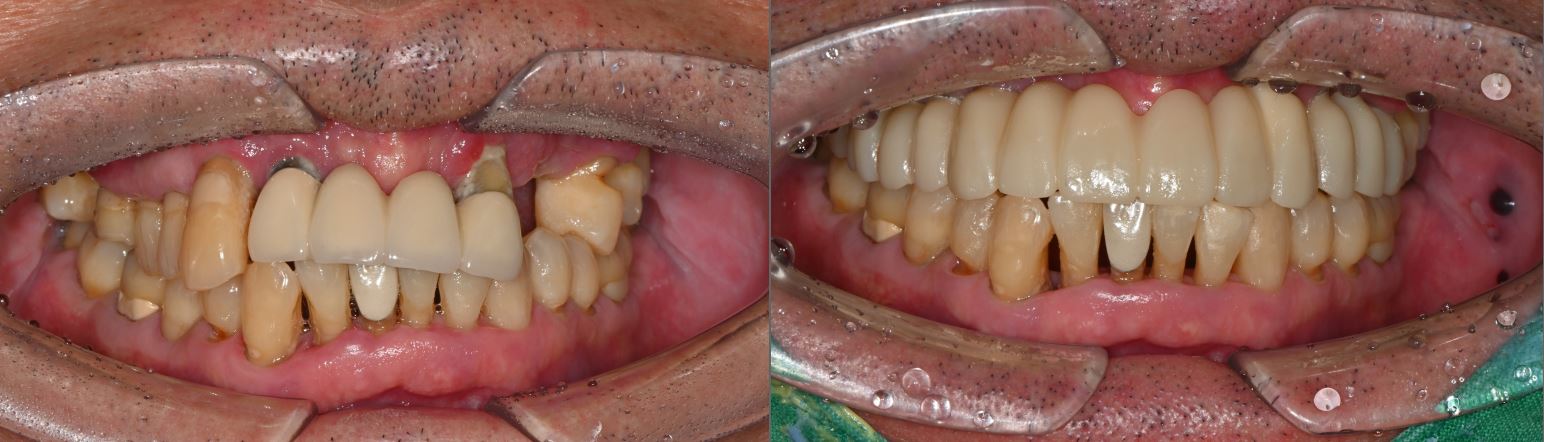

치료전후사진